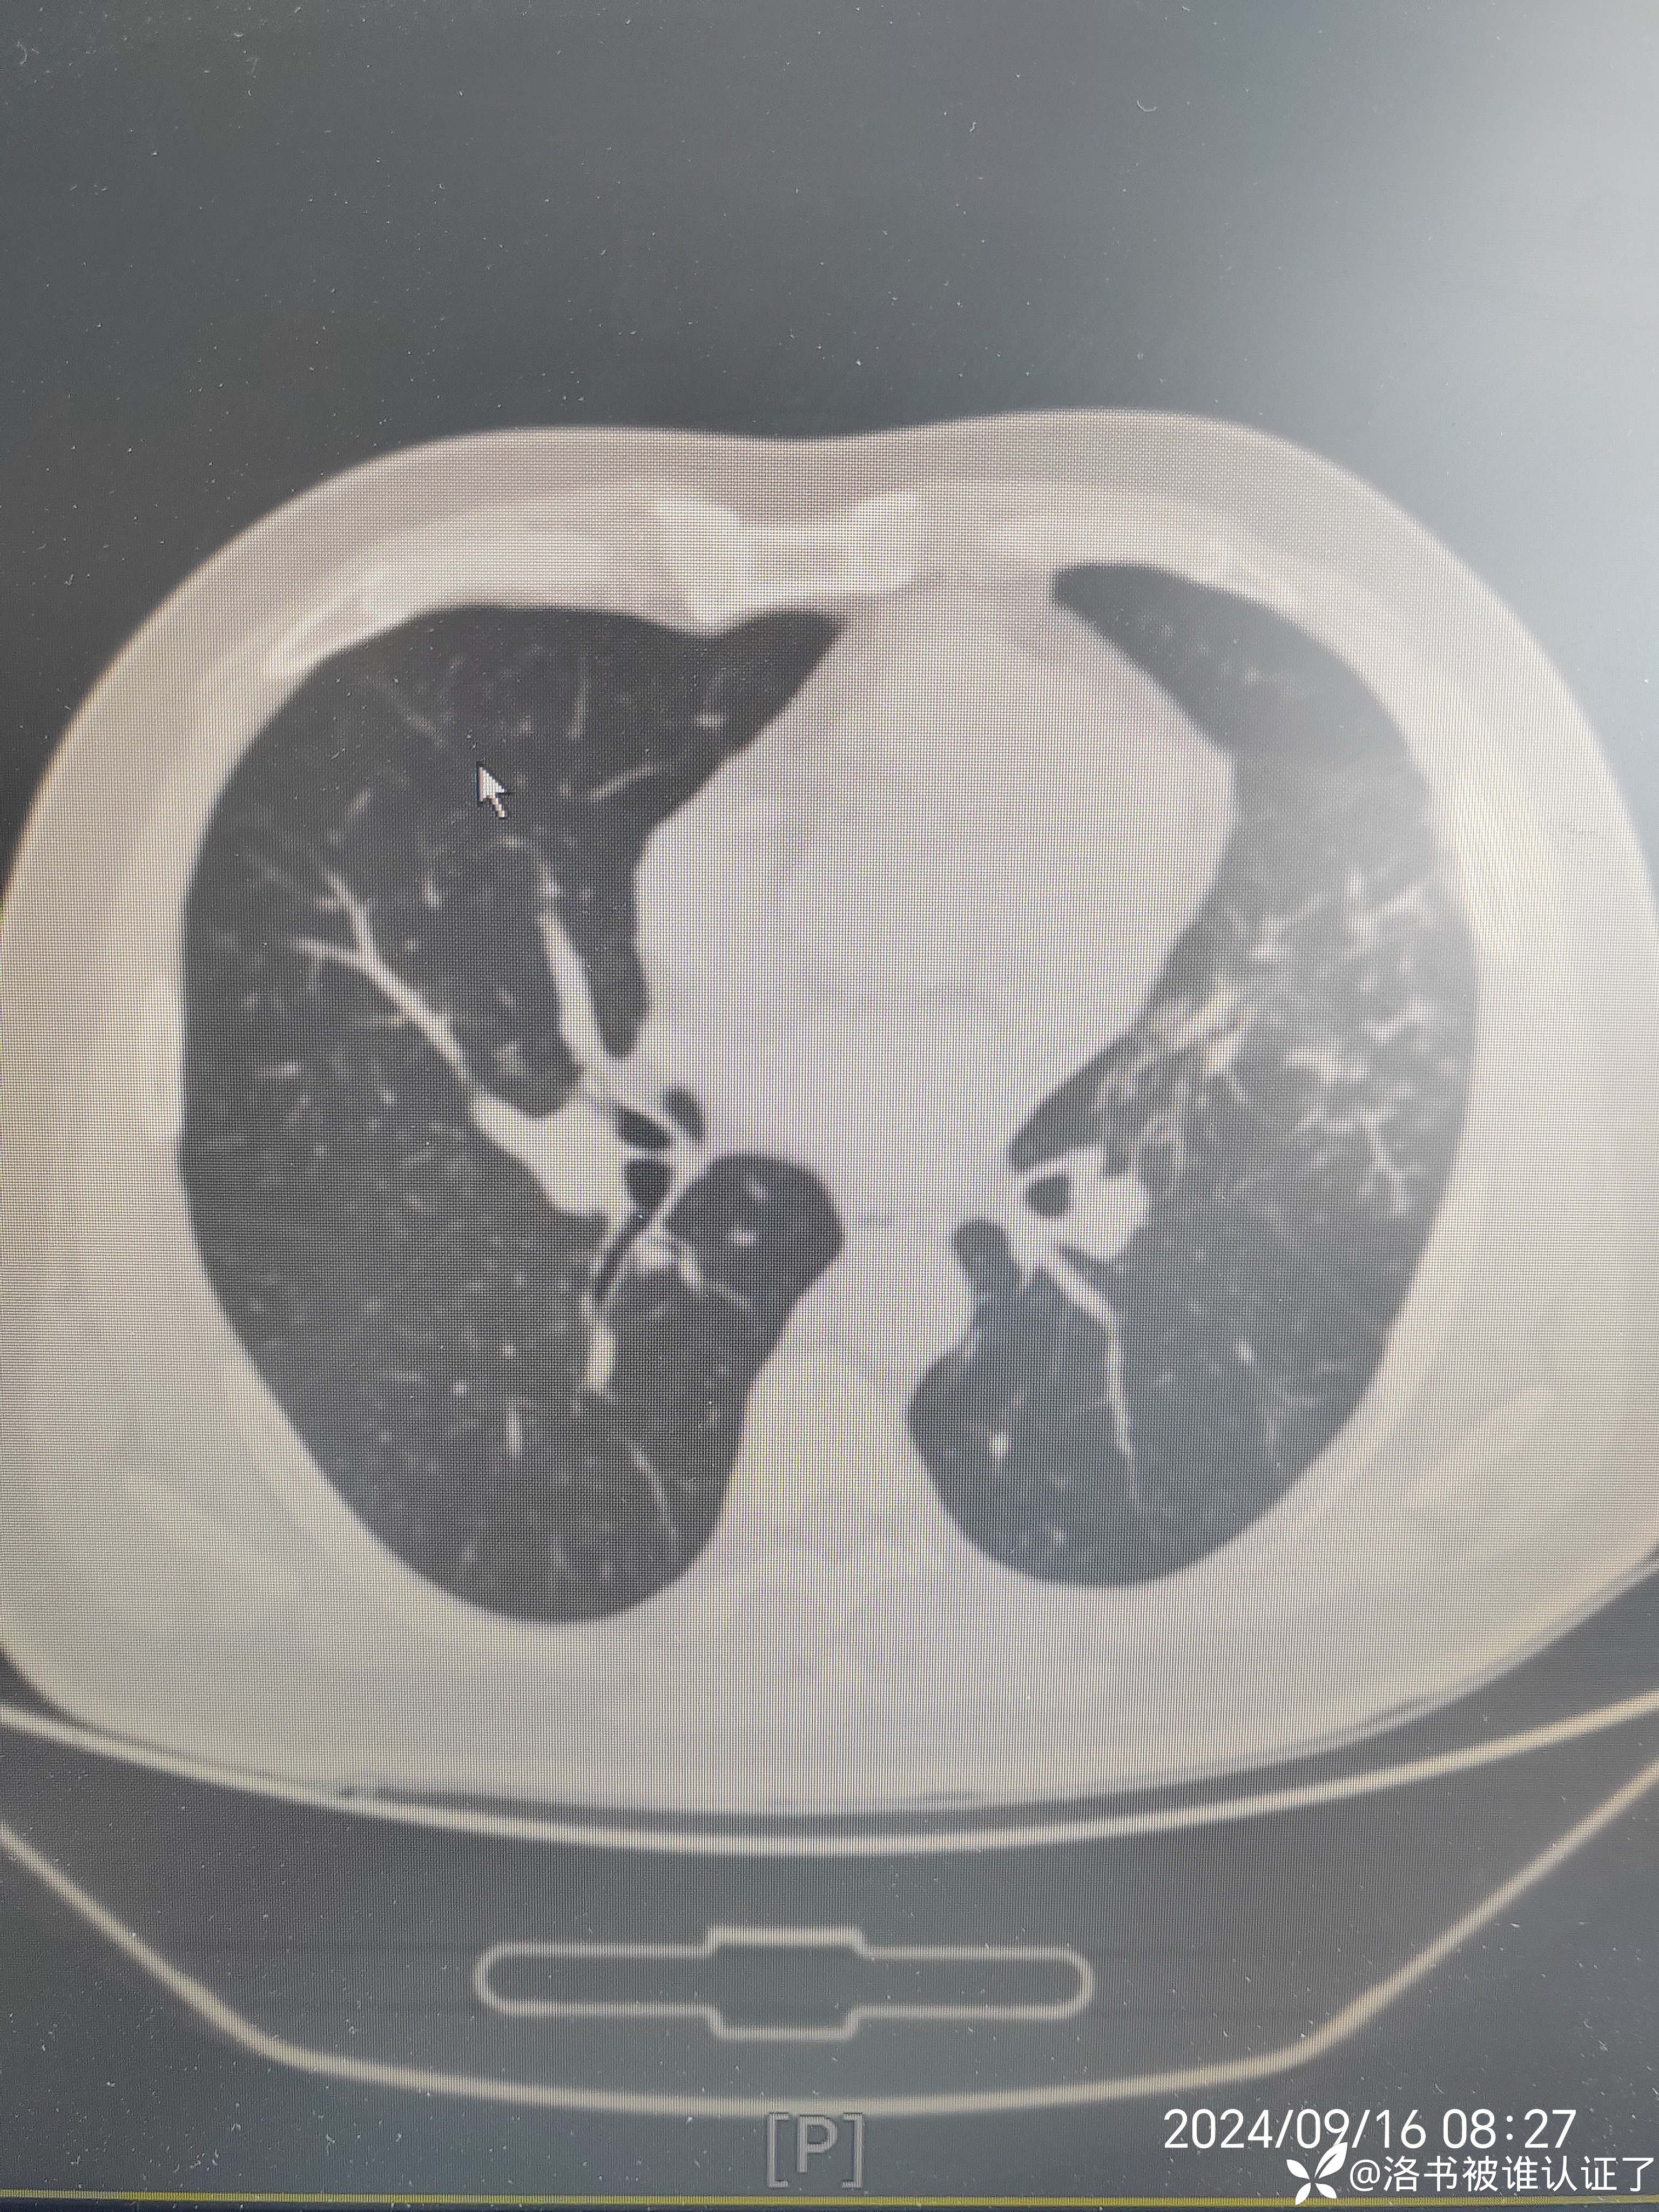

【检查】胸部CT示肺炎。

【临床诊断】:肺炎